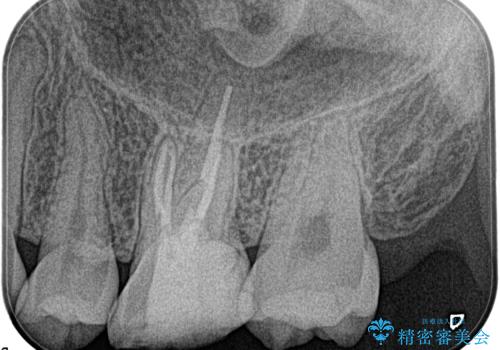

【根管治療】ズーンと痛い歯の治療。

- 奥歯付近がジーンと痛いことを主訴に来院されました。

左上7番の歯は、歯髄検査にて反応を示し、歯周ポケットはありませんでした。

親知らず抜歯を行い、痛みの変化や歯根吸収の有無を確認したのち、抜髄処置を行っています。

症状改善し、遠心の骨の回復も認めます。

バイオセラミックシーラーを使用して根管充填を行っています。